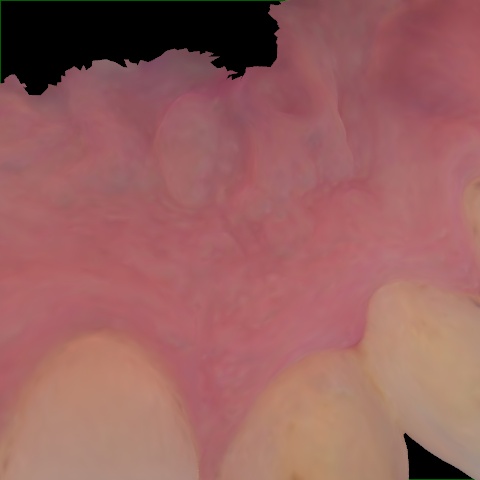

NHD39969

Annotated as "Good"

Original Image Rendering Image